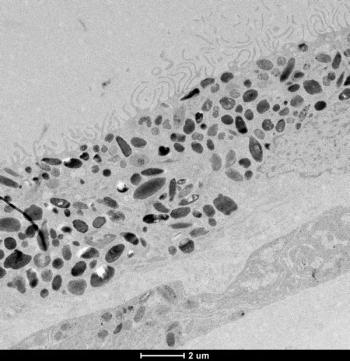

In a presentation at the Angiogenesis, Exudation, and Degeneration 2023 meeting hosted by Bascom Palmer Eye Institute, Baruch Kupperman, MD, PhD, detailed research in which investigators evaluated risuteganib for safety and effectiveness in patients with dry AMD.